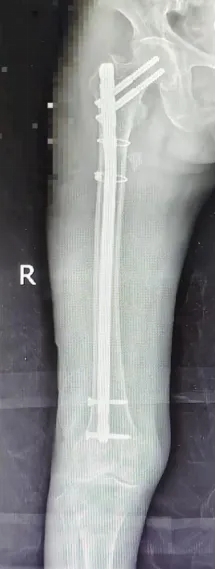

经多学科专家诊断:陈阿婆右股骨近端粉碎性骨折,并伴有肋骨骨折、胸腔积液和高血压——对高龄长者而言,任何一项都可能成为“致命一击”。在救治过程中既要应对骨折剧痛,又要控制高血压风险,同时要处理肋骨骨折与胸腔积液可能引发的呼吸问题。

会诊次日,在崔红旺主任带领下,创伤科手术团队为患者实施了微创内固定手术。专家们屏息凝神,在极小创伤下完成骨折精准复位与固定。一个多小时后,手术圆满成功——全程出血少、时间短,成功跨越高龄与多基础病的双重手术难关。